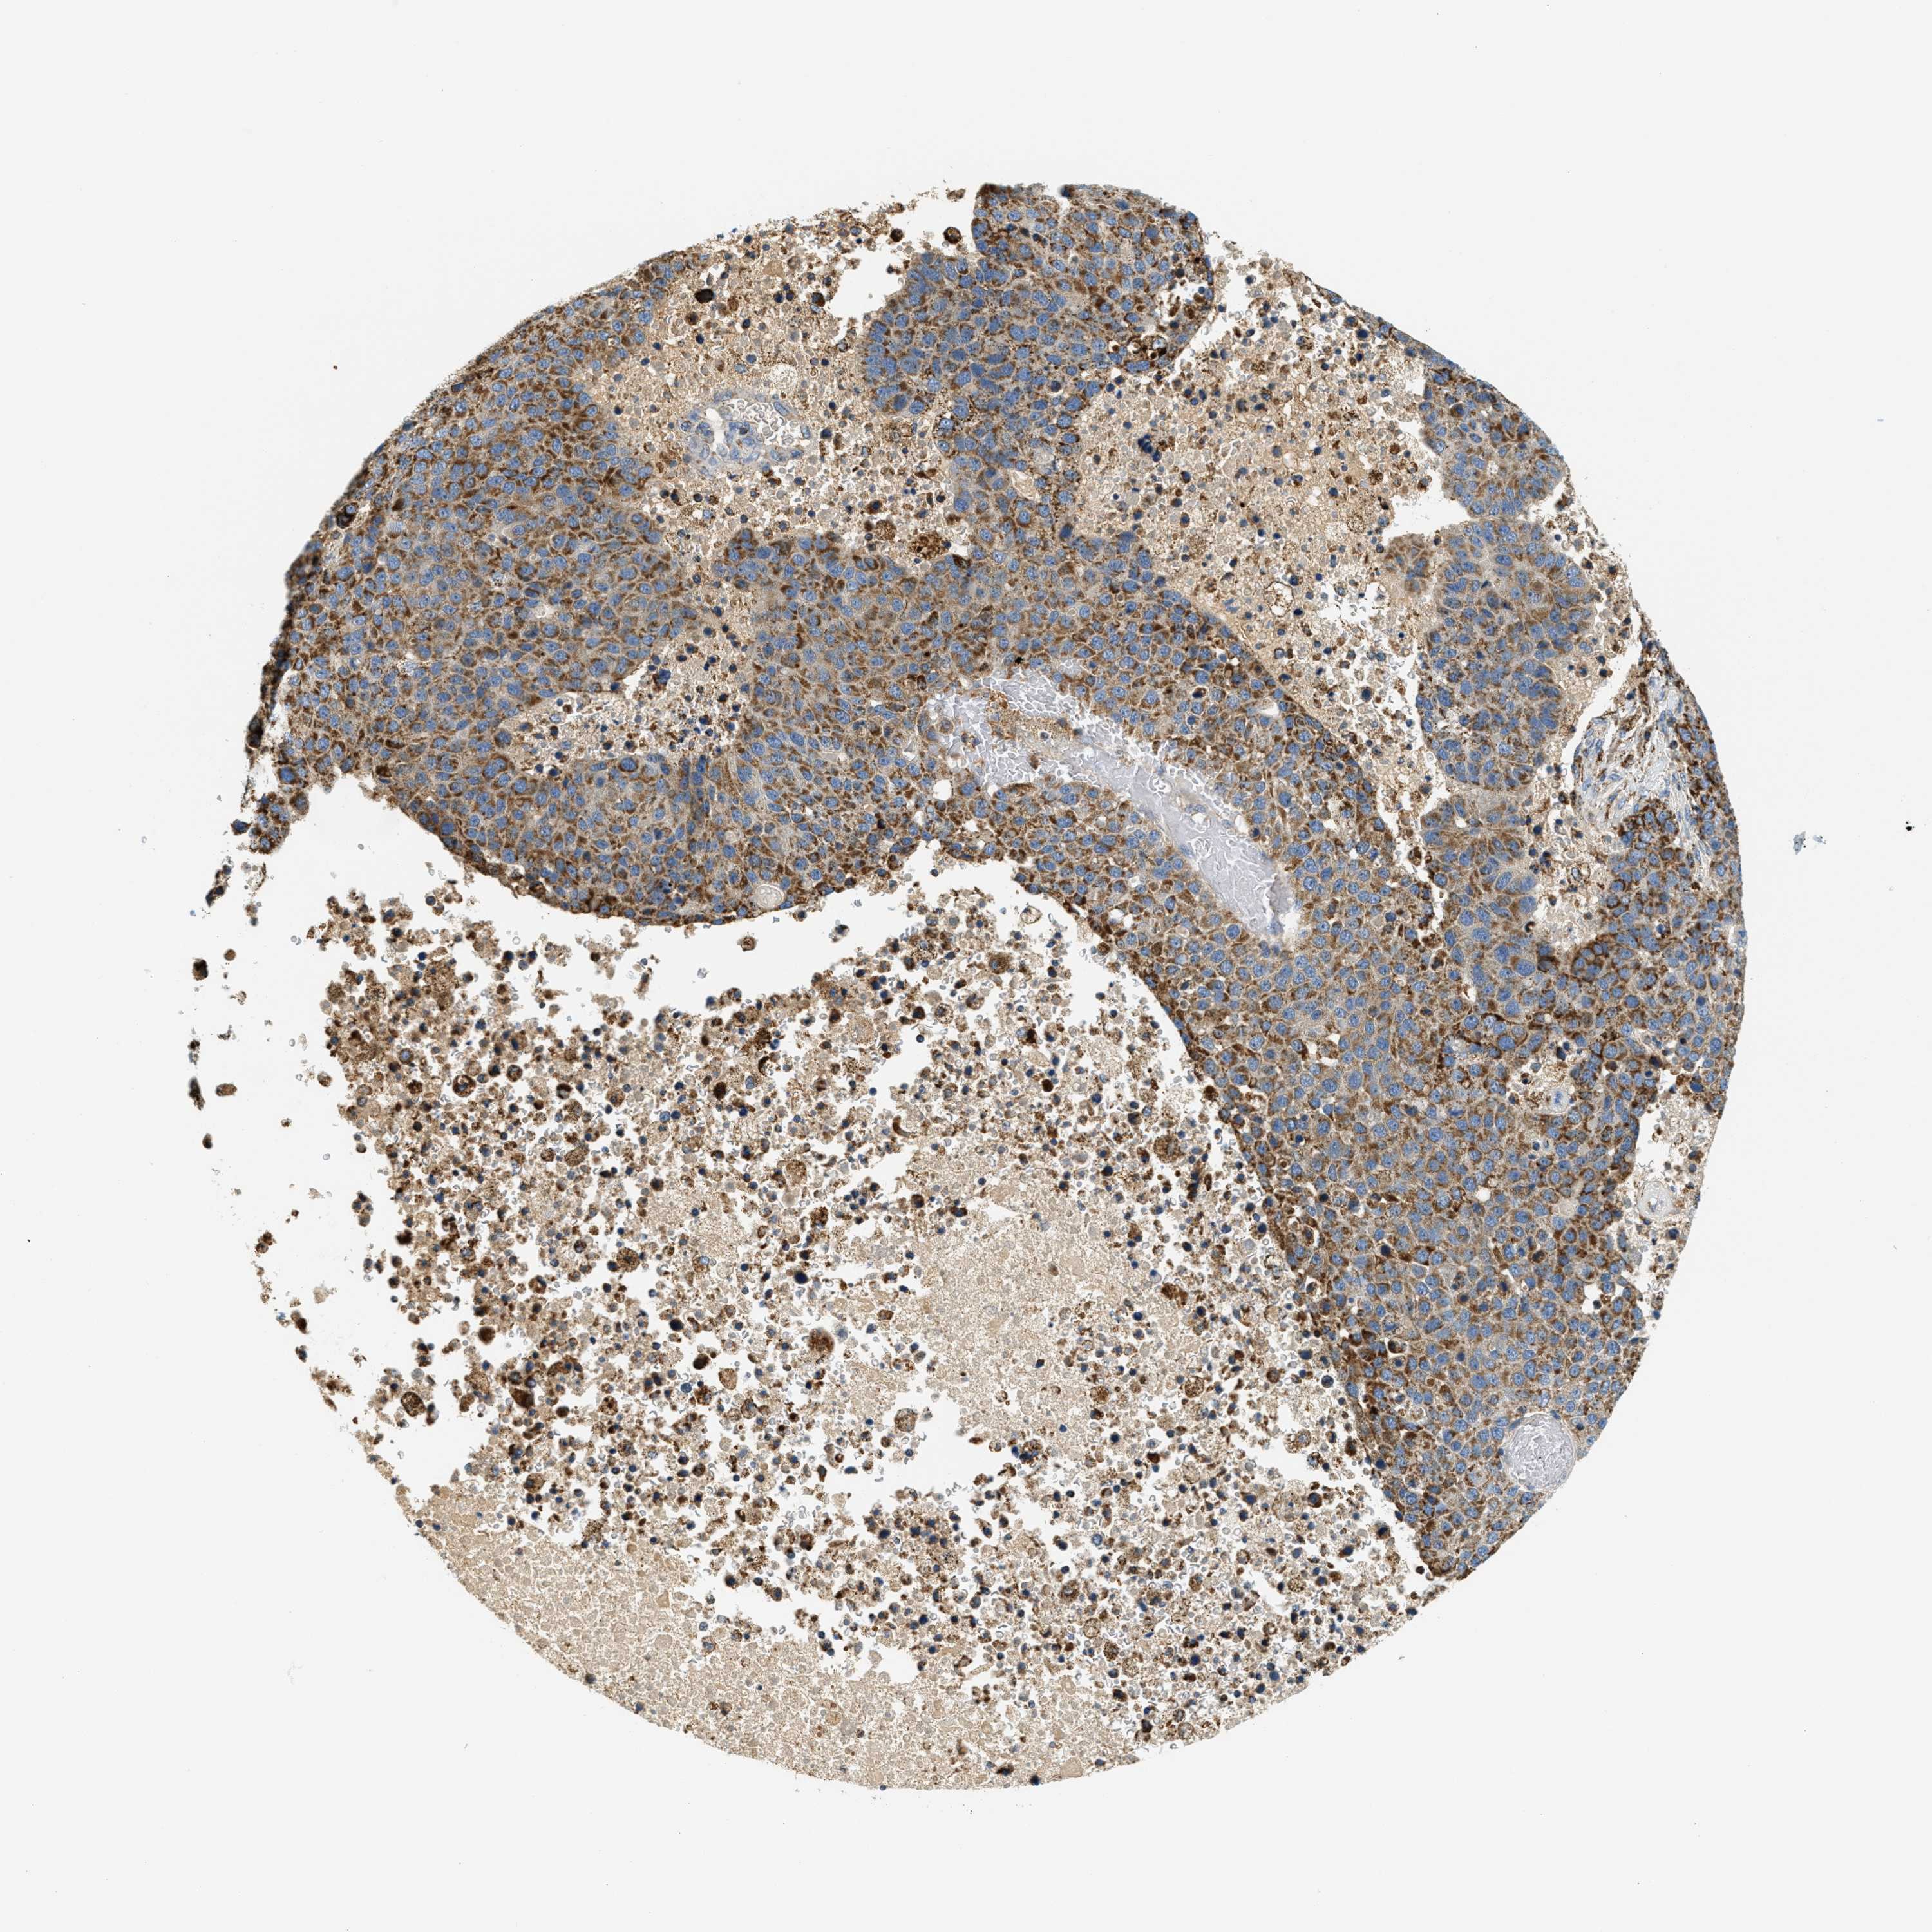

PANCREATIC CANCER - Protein expressioni

A mouse-over function shows sample information and annotation data. Click on an image to view it in a full screen mode. Samples can be filtered based on level of antibody staining by selecting one or several of the following categories: high, medium, low and not detected. The assay and annotation is described here.

Note that samples used for immunohistochemistry by the Human Protein Atlas do not correspond to samples in the TCGA dataset.

Antibody stainingi

Antibody staining in the annotated cell types in the current human tissue is reported as not detected, low, medium, or high, based on conventional immunohistochemistry profiling in selected tissues. This score is based on the combination of the staining intensity and fraction of stained cells.

Each image is clickable and will lead to virtual microscopy that enables deeper exploration of all samples and also displays staining intensity scores, fraction scores and subcellular localization as well as patient and tissue information for each sample.

Antibody HPA017379

Staining

High

Medium

Low

Not detected

Intensity

Strong

Moderate

Weak

Negative

Quantity

>75%

75%-25%

<25%

None

Location

Nuclear

Cytoplasmic/membranous

Cytoplasmic/membranous,nuclear

Adenocarcinoma, NOS